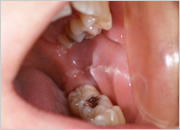

- CHIPPING

- チッピングやフラクチャー(破折)

- チッピング

- 奥歯の歯冠破折

- 前歯の歯冠破折